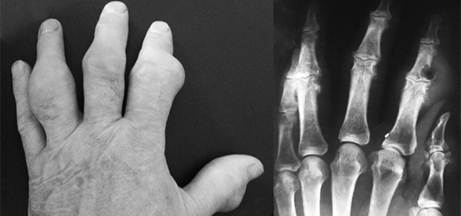

Рентгенография пораженных суставов играет вспомогательную роль в диагностике подагры: в ранних стадиях выявляется остеопороз эпифизов, сужение суставной щели, деструкция суставной поверхности, микрокисты; в поздних стадиях - характерный для подагры симптом "пробойника" (крупные кисты округлой формы, окруженные плотным валиком, крупные краевые узуры, остеолиз фаланг) (рис.3-4).

крупная киста с грубыми склеротическими стенками

Рис. 3-4. Многочисленные крупные тофусы на пальцах кистей; та же кисть на рентгенограмме.